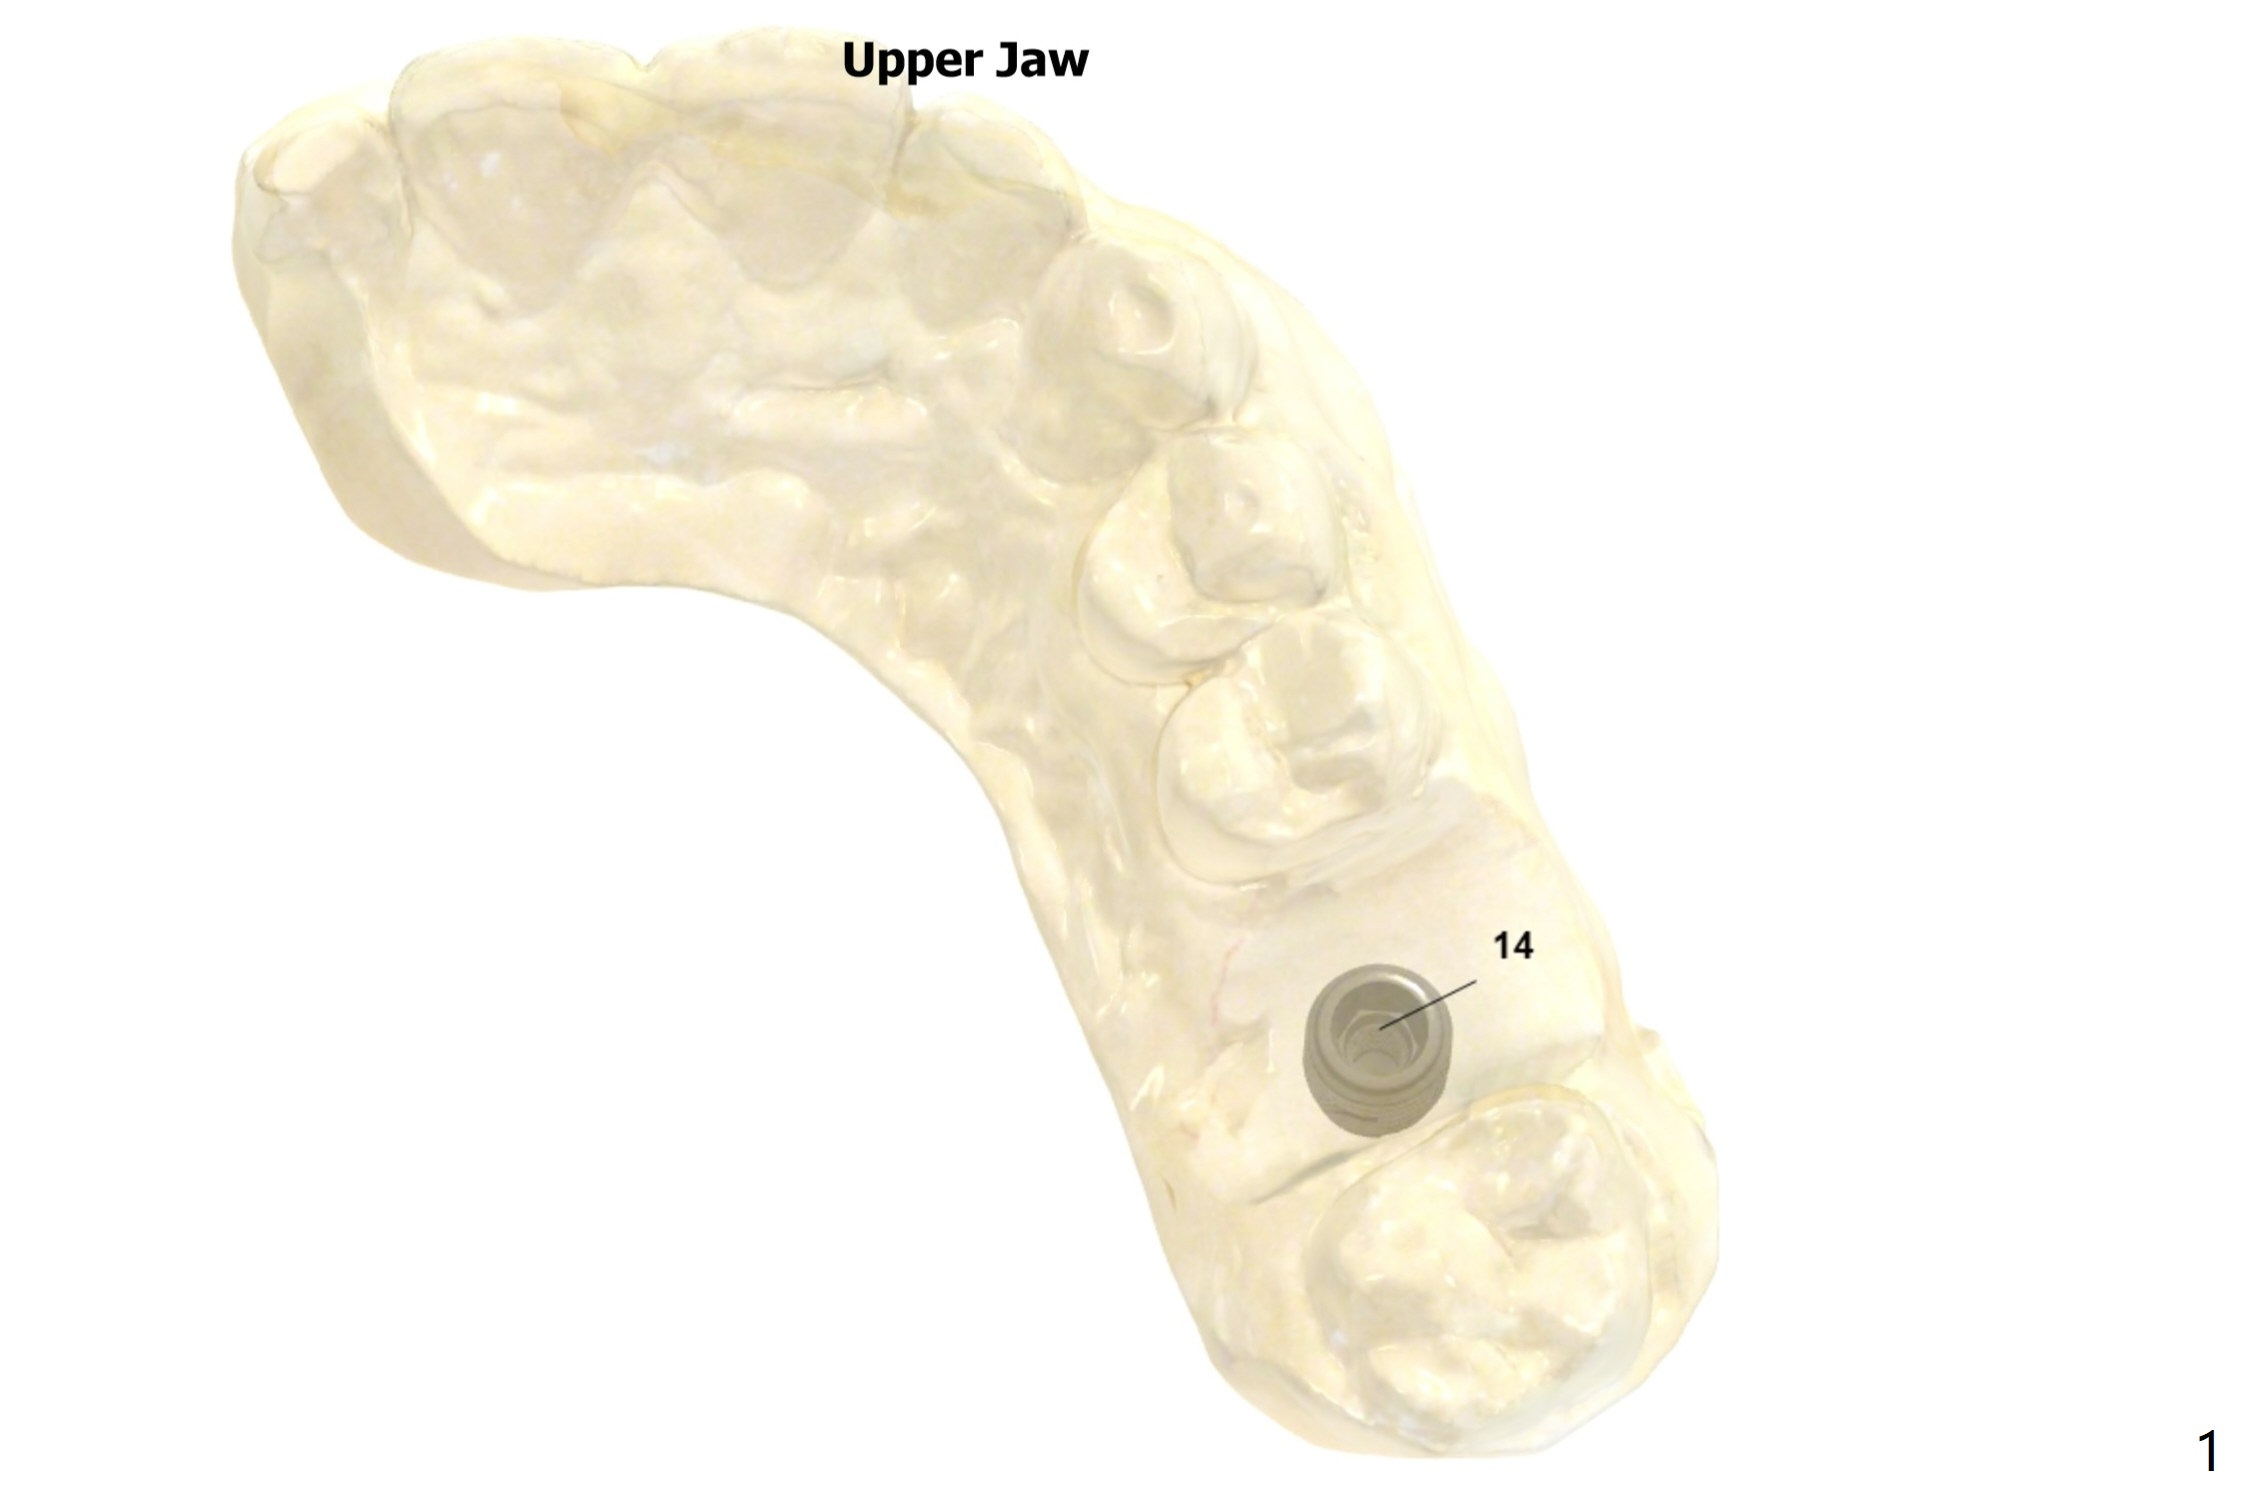

Short Implant with Palatal Shield

Try to place a 5x9 mm implant. After use of the last 2nd drill (and probe), use the narrowest drill to the depth and probe.